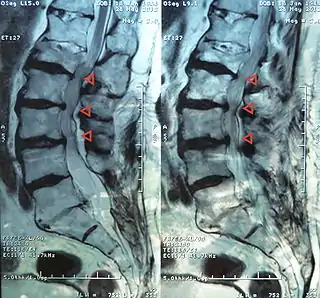

![]() Estenosis de canal a nivel L4-3-2-1 | ||

El término estenosis medular lumbar incluye la estenosis del canal espinal, el receso lateral y los agujeros o forámenes intervertebrales siendo más común en los niveles L2 a L5 y constituye una de las causas más comunes de dolor en la espalda y en las extremidades inferiores por opresión de la médula y de las raíces nerviosas espinales.[2]